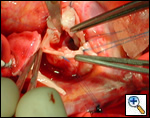

The operative approach is through a median sternotomy with the use of cardiopulmonary bypass and bicaval venous cannulation. The first dose of cold blood cardioplegia is antegrade; the remaining doses are retrograde.

High ascending aortic cannulation adjacent to the innominate artery for maximum exposure of the ascending aorta and to allow length for positioning of the patch in the ascending aorta.

One dose of antegrade cardioplegia followed by retrograde cardioplegia.

Pulmonary homograft or pericardial patches (tanned in glutaraldehyde) for the “shields”. These patches should not be too large – this will lead to aortic insufficiency.

First coronary sinus incision in noncoronary sinus to facilitate exposure of the incisions into the coronary orifice sinuses.

In most cases, the right coronary artery sinus should be opened to the left of the coronary orifice and the left coronary artery sinus to the right of the coronary orifice. Occasionally one may not have enough room between a coronary orifice and the aortic valve; in this case the incision site should be tailored to the situation.

Ensure similar orifice sizes between the proximal and distal ascending aorta after patch augmentation by the use of a sizing dilator.

Transesophageal echocardiography to assess completeness of repair, coronary blood flow postoperatively, wall motion abnormalities, and adequacy of aortic valve.